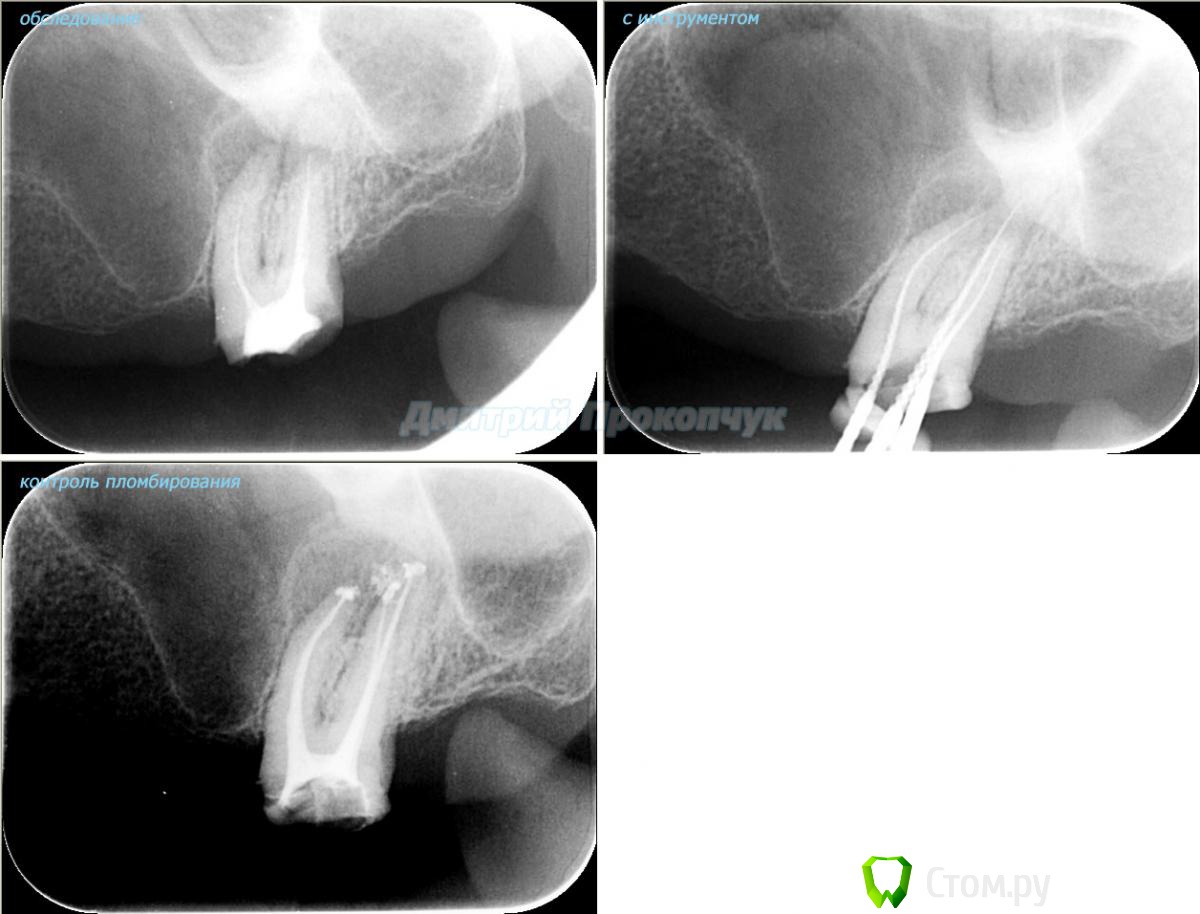

punkrat Опубликовано 16 сентября, 2014 Поделиться Опубликовано 16 сентября, 2014 Коллеги, тема , возможно, не имеет смысла просто приятная мне эндодонтия, сохранил с предыдущего места работы. Да, будь я проклят, я все знаю, НИГДЕ НЕТ КОФЕРА, на новом месте с этим норм. В общем если посчитаете, что я недостоин постить тут свои снимки, то так тому и быть, удалю тему.. 01. плановый ретрит 46ого и результат через 7 месяцев. Осложняющим моментом тут было то, что длина каналов была около 26 мм... 02. первичное эндо 34 (подготовка к ортопедии) + бонус - ретрит 35 03. ретрит 26 (подготовка к ортопедии) 04. ретрит 15, 16 (подготовка к ортопедии). основная сложность была в ретрите 15 - он был запломбирован термафилами, да еще снабжен свш... 05. ретрит 27 (подготовка к ортопедии). Ничего особенного, со временем посмотрим какова будет убыль этого совсем немаленького разрежения 06. ретрит 13. Разумеется пришлось выбивать вкладку, а потом еще попилить 3-4 миллиметра цемента, но, таки попилил куда нужно... 07. ретрит 17 (подготовка к ортопедии). В данном случае я, кажется, потратил больше времени на снятие литого моста, чем на лечение 17)) 08. ретрит 16 (подготовка к ортопедии). Снимка с инструментом нету, поскольку, визиограф сломался и его делал на пленку. 15 разумеется тоже перелечен... 09. плановый ретрит 16 10. первичное эндо 36, рядовой случай что дистальный щечный удалось найти не сразу, он был спрятан под нависающим дентиклем 11. ретрит 12, 11 (подготовка к ортопедии). Казалось бы, рядовой случай, если бы корневые каналы обоих зубов не были бы налухо забиты резорцин-формалиновой смесью... 12. ребенок 9ти лет, острый пульпит 46, попробовал оставить витальным. Пока полет нормальный, но даже если придется делать эндо в последствии, лучше когда оно будет сделано в более старшем возрасте... 13 Ссылка на комментарий